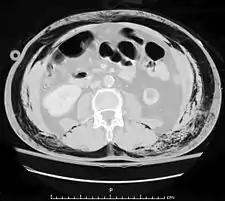

La ecografía puede detectar fluidos como la sangre o contenido gastrointestinal en la cavidad abdominal y es un procedimiento no invasivo y relativamente seguro para el paciente.[4] La tomografía computarizada de exploración es la técnica preferida para las personas que no están en riesgo inmediato de choque,[13] pero ya que la ecografía se puede realizar en una sala de emergencia, este último se recomienda para personas que no están lo suficientemente estables como para pasar al tomógrafo.[1] Sin embargo, los pacientes con traumatismo abdominal con frecuencia necesitan la tomografía computarizada para otros traumatismos concomitantes, por ejemplo, cráneo o tórax. En estos casos, la TAC abdominal se puede realizar al mismo tiempo, sin perder tiempo en la atención de los pacientes.[4]

La laparoscopia diagnósitica o la laparotomía exploratoria también puede llevarse a cabo si otros métodos de diagnósticos no arrojan resultados concluyentes.[3] La tomografía sigue siendo una importante herramienta de diagnóstico debido a su especificidad para las lesiones hepáticas, esplénicas y renales. El papel de la laparoscopia puede verse ampliada en el futuro con la disponibilidad de laparoscopio de menor calibre que pueda ser insertado bajo anestesia local.[13]